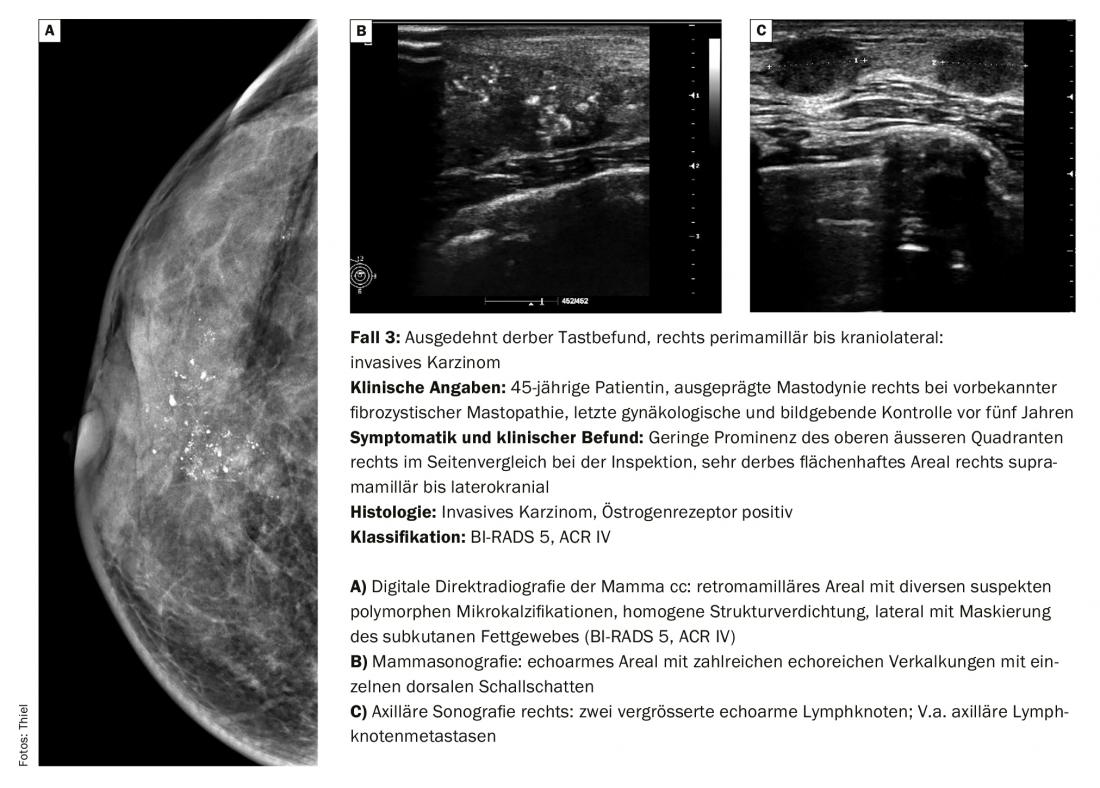

O diagnóstico diferencial dos nódulos mamários palpados corresponde em cerca de 90% a alterações benignas tais como fibroadenomas, cistos, mastopatias fibrocísticas e outras alterações mais raras. Contudo, o carcinoma é de esperar em cerca de 10% dos casos [1]. Os resultados da palpação nestes casos são geralmente nódulos grosseiros. As pequenas descobertas podem ainda ser móveis, os tumores maiores menos. Contudo, nem todas as malignidades são clinicamente evidentes (caso 2) ou, no caso de estrutura mamária densa e palpação suspeita, também podem ser claramente reconhecidas mamograficamente (caso 3).

O padrão do American College of Radiology (ACR) para o “Breast Imaging Reporting and Data System” (BIRADS) e a classificação ACR também é válido para doenças malignas.